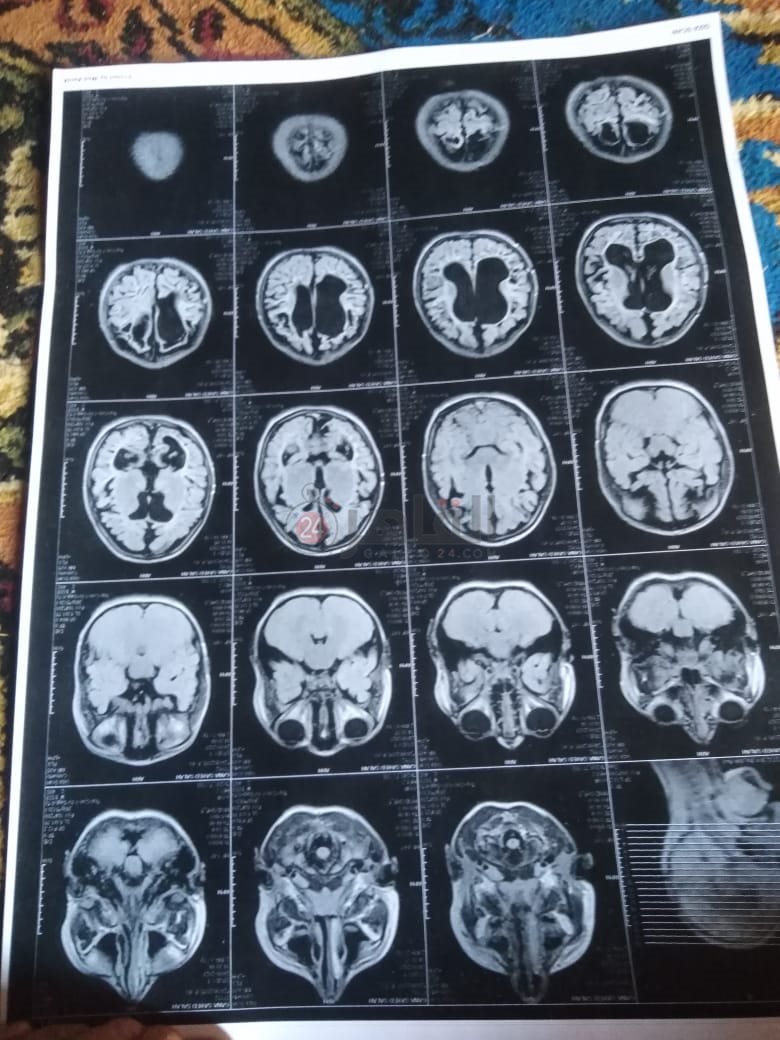

من جانبه، قال صلاح سيد، والد الطفلة جنى صلاح، إن ابنته تعاني من ضمور في المخ منذ ولادتها، نتيجة خطأ طبي، أدى إلى نقص كبير في الأكسجين لديها.

وأضاف في تصريحات خاصة لـ "القاهرة 24": "جنى تبلغ من العمر 6 سنوات، لا تستطيع المشي أو الوقوف على قدميها، نتيجة إصابتها بضمور في المخ منذ ولادتها".

وتابع: "مكنتش بتتحرك خالص، وجسمها طري، روحت كشفت عليها، وعملت أشعة وتحاليل كتير، أتأكدنا إصابتها بضمور في المخ"، مضيفًا:" مش بتعرف تأكل احنا اللي بنأكلها، هي عقلها كويس لكن مش بتتحرك ولا تتكلم".